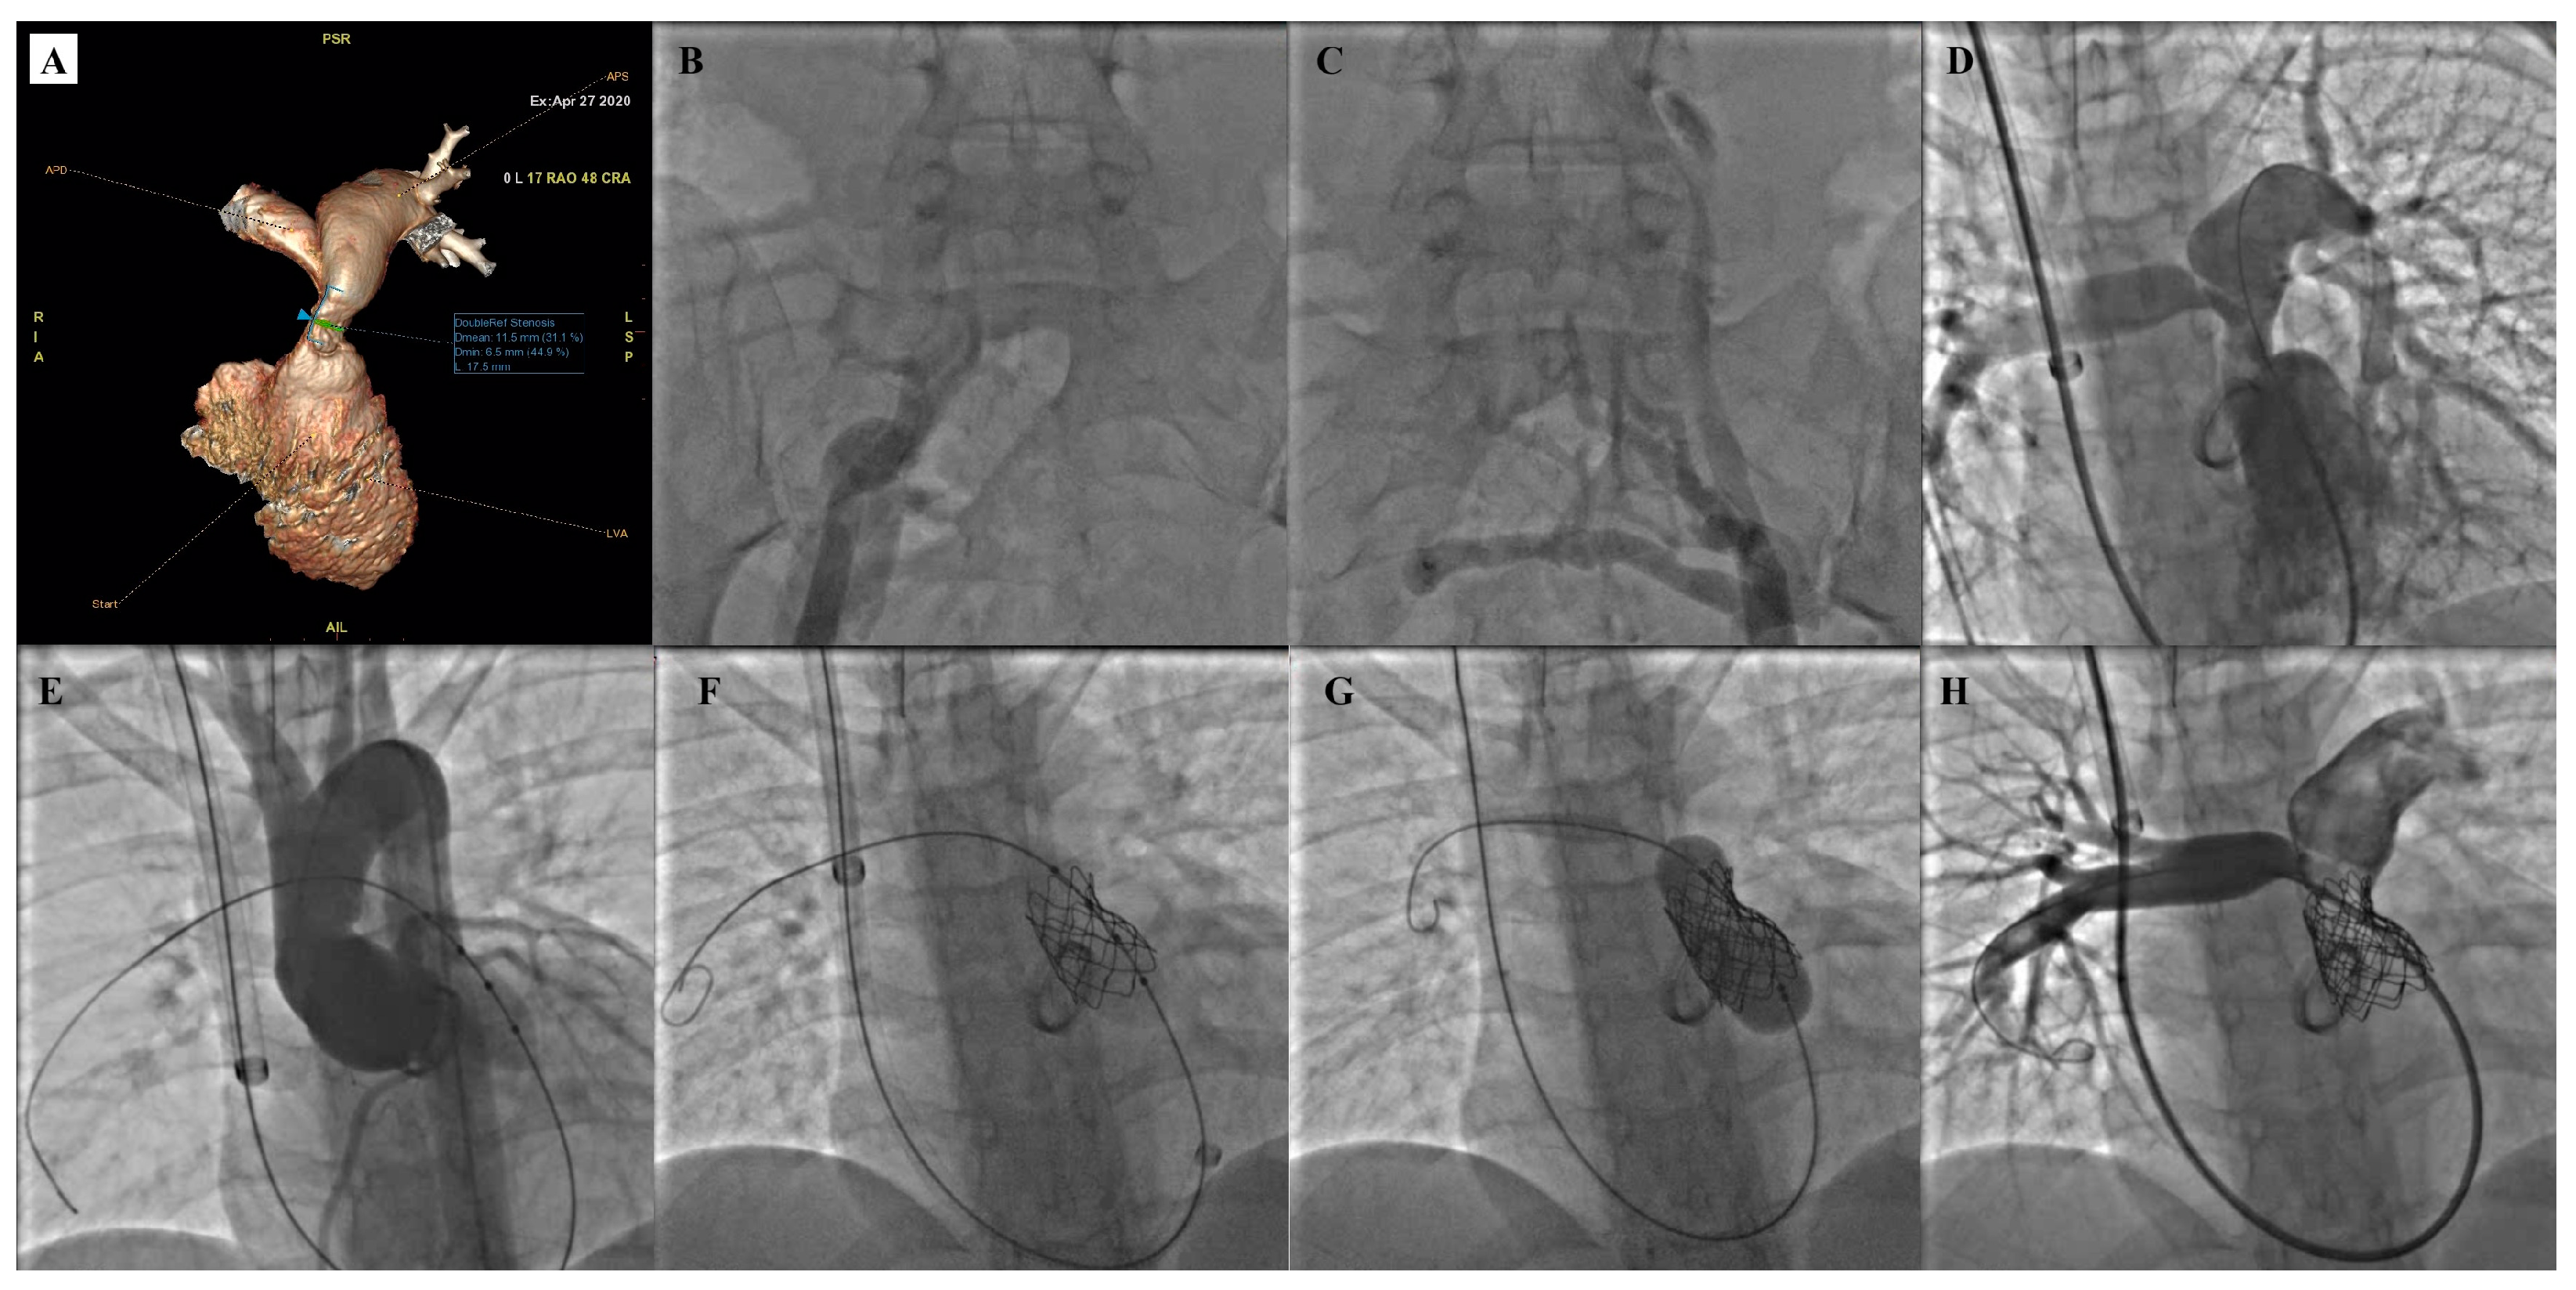

- Garay, F.; Pan, X.; Zhang, Y.J.; Wang, C.; Springmuller, D. Early experience with the Venus P-Valve for percutaneous pulmonary valve implantation in native outflow tract. Neth. Heart J. 2017, 25, 76–81. [Google Scholar] [CrossRef] [PubMed]

- Morgan, G.; Prachasilchai, P.; Promphan, W.; Rosenthal, E.; Sivakumar, K.; Kappanayil, M.; Sakidjan, I.; Walsh, K.P.; Kenny, D.; Thomson, J.; et al. Medium-term results of percutaneous pulmonary valve implantation using the Venus P-Valve: International experience. EuroIntervention 2019, 14, 1363–1370. [Google Scholar] [CrossRef] [PubMed]

- Jin, Q.; Long, Y.; Zhang, G.; Pan, X.; Chen, M.; Feng, Y.; Liu, J.; Yu, S.; Pan, W.; Zhou, D.; et al. Five-year follow-up after percutaneous pulmonary valve implantation using the Venus P-Valve system for patients with pulmonary regurgitation and an enlarged native right ventricular outflow tract. Catheter. Cardiovasc. Interv. 2024, 103, 359–366. [Google Scholar] [CrossRef]